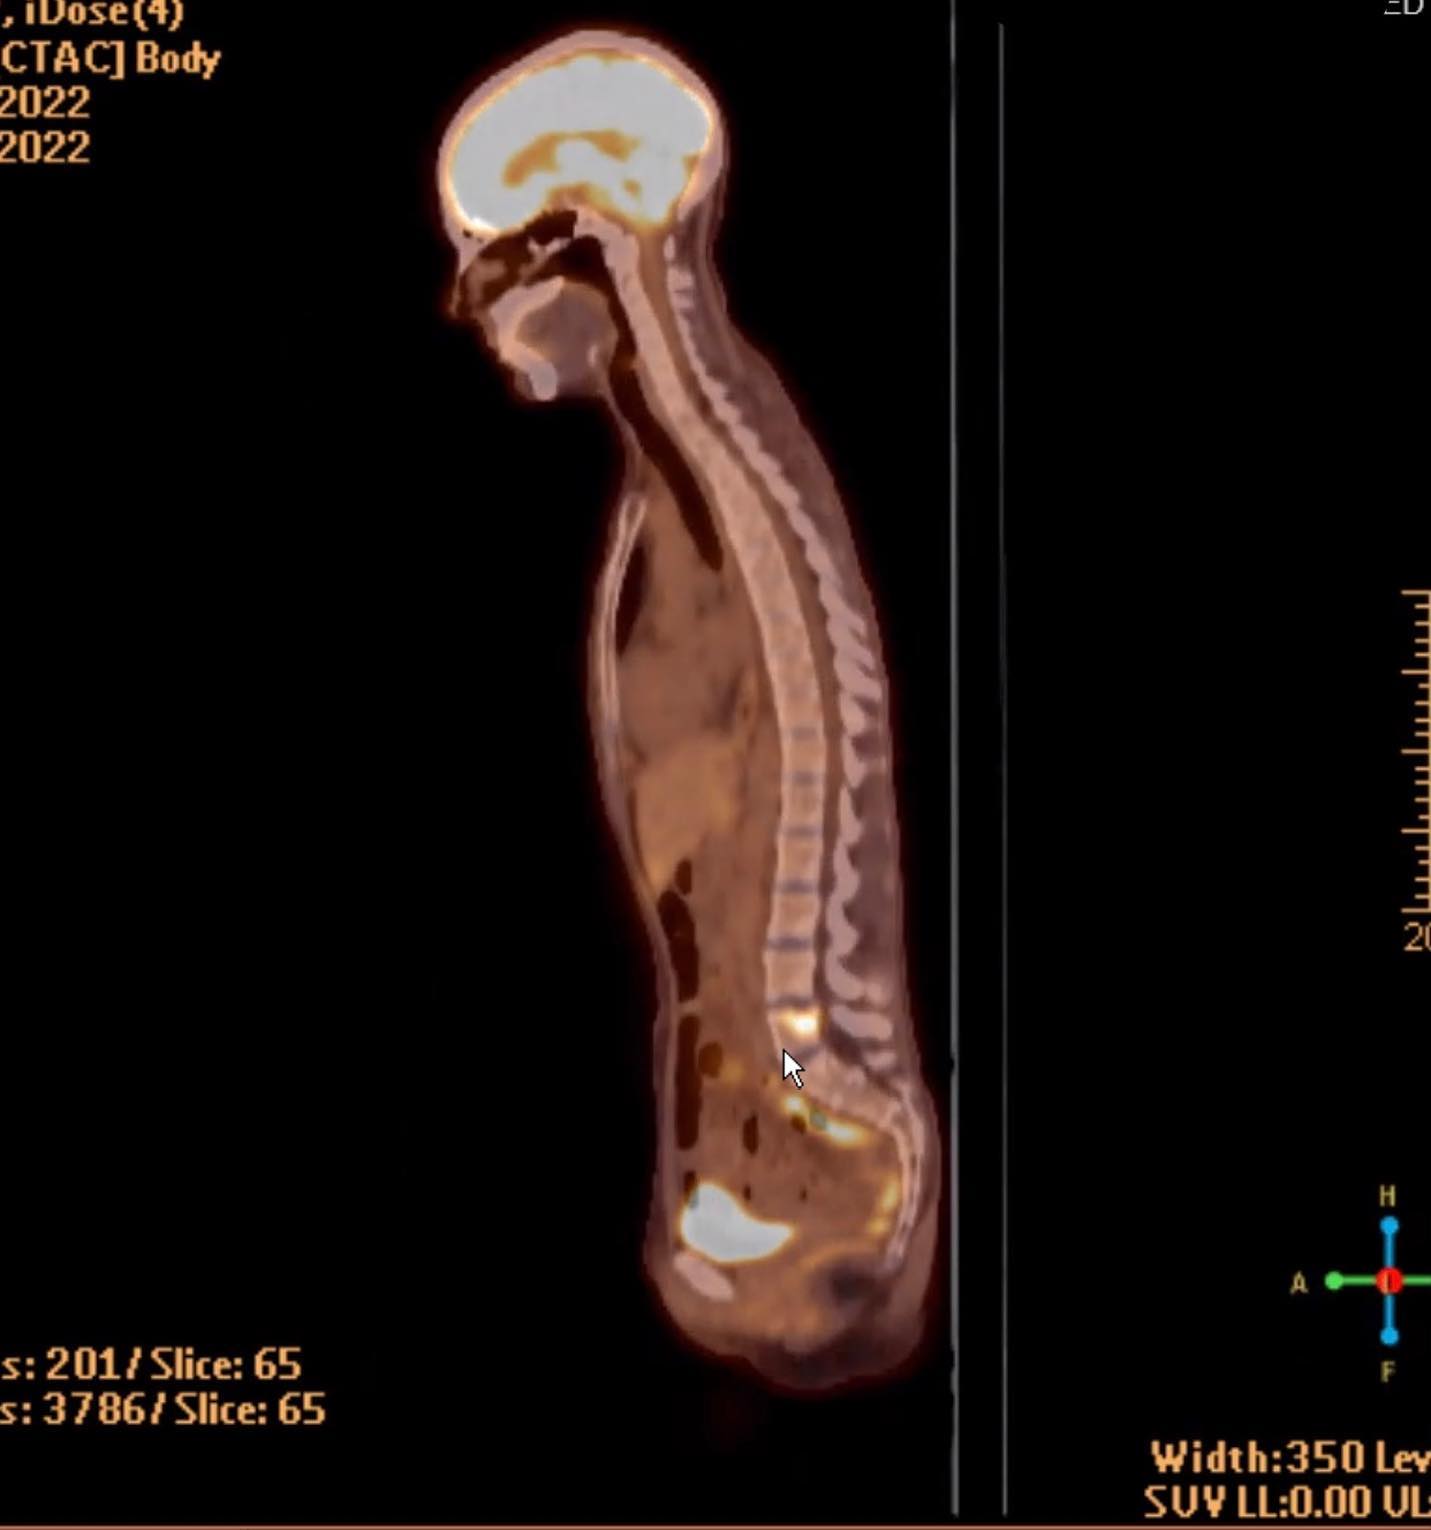

something big to share is that i’ve qualified for a trial. it’s being done all over the country and one base is santa rosa. it’s with a medicine called Trodelvy - (which is not the trial drug and that was the next one offered to me) and another one called magrolizumab. i have big and complicated and honestly just unreachable feelings about this. a couple doctors have told me i’ve got weeks left of my life. Other doctors say this could prolong my life with genuine quality. it could not work at all, like the others i tried. the disease progressed at a horrifying rate on the yew and keytruda. it could work in astonishing ways- like for people who i interact with on forums who have achieved “no evidence of disease” on trodelvy after trying many other courses of treatment. continued in comments…

i’ve had some good relief from pain and anxiety- and realized i was in so much pain when i checked myself in late saturday/early sunday that i didn’t even remember a lot that happened- i had a CT scan i didn’t know about.